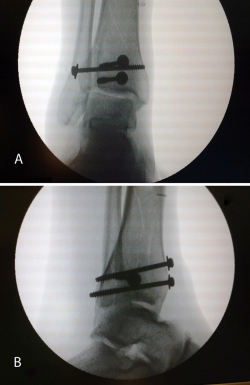

Figura 19. Colocación del tornillo en el Tillaux con la extremidad en tracción y posteriormente la placa MIPO (minimally invasive plate osteosynthesis).

Figura 20. Radiografías postoperatorias y resultado final con movilidad completa en flexoextensión del tobillo.